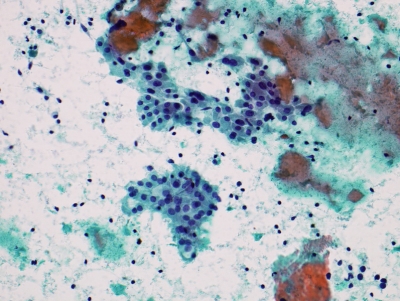

Home > BENIGN > Lymphocytic (Hashimoto) thyroiditis

Lymphocytes and Hurthle cells (oncocytic metaplasia)

Keywords: Chronic Lymphocytic Thyroiditis (Hashimoto) lymphocytes Hurthle cells oncocytes